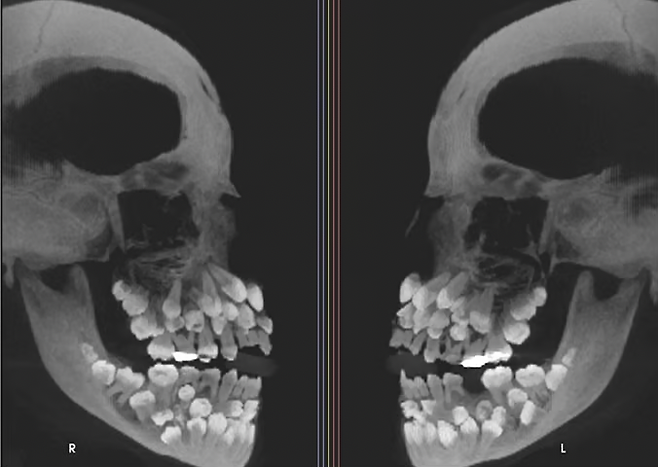

11세 소녀의 입안에서 치아가 81개나 발견돼 학계에서 관심을 받고 있다.

최근 VN익스프레스 등 외신은 브라질에 사는 11세 소녀의 입안에서 유치 18개와 영구치 32개, 과잉치 31개 등 총 81개 치아가 발견됐다고 전했다.

![11세 소녀 입안에서 치아가 81개나 발견돼 학계가 관심을 보이고 있다. [사진 출처 = VN익스프레스]](https://img2.daumcdn.net/thumb/R658x0.q70/?fname=https://t1.daumcdn.net/news/202507/18/mk/20250718070308085izfu.png)

최근 VN익스프레스 등 외신은 브라질에 사는 11세 소녀의 입안에서 유치 18개와 영구치 32개, 과잉치 31개 등 총 81개 치아가 발견됐다고 전했다. 소녀가 위쪽 유치 1개를 뽑기 위해 병원을 찾아 엑스레이를 촬영하면서 이같은 사실이 알려졌다.

보통 성인 기준 32개인 정상 치아 수를 넘겨 추가 치아가 발견되는 것을 ‘다발성 과잉치증’으로 일컫는다. 이 질환은 잇몸 속에 치아가 매복돼 있어 정상 치아의 맹출(잇몸 위로 나는 과정)을 방해하거나 치아 배열이 어긋나는 등의 문제를 일으키기도 한다. 또 매복된 과잉치 주변에 물혹이 생기는 등 문제를 일으킬 수 있다.

다발성 과잉치증은 선천적인 것으로 1~2개의 과잉치만 발견되는 경우는 종종 있다. 위의 사례처럼 30개가 넘는 과잉치가 확인된 사례는 전 세계적으로 드물다. 브라질 미나스제라이스주 주이스지포라 연방대학교 치과병원 연구팀이 진료 중 확인했고, 미국 치과교정·악안면외과학회지에 보고됐다.